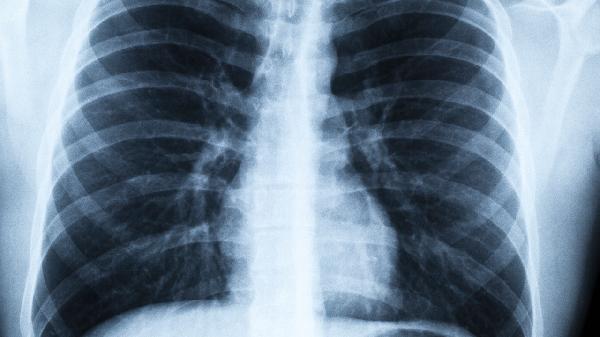

肺气肿这个“隐形杀手”正在悄悄侵袭越来越多人的健康,它就像个慢慢漏气的气球,让呼吸变得越来越费力。很多人直到爬楼梯开始大喘气才意识到问题严重性,但此时肺部损伤往往已不可逆转。